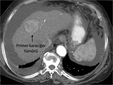

Karaciğer Lekeleri: Belirtileri ve TedavisiKaraciğer, vücudumuzun en büyük organlarından biri olup, birçok önemli işlevi bulunmaktadır. Karaciğer lekeleri, bu organ üzerinde meydana gelen anormal değişiklikler veya lezyonlardır. Bu lekeler, genellikle tesadüfen yapılan görüntüleme testleri sırasında fark edilir ve çeşitli nedenlerden kaynaklanabilir. Bu makalede, karaciğer lekelerinin belirtileri, nedenleri ve tedavi yöntemleri detaylı bir şekilde incelenecektir. Karaciğer Lekeleri Nedir?Karaciğer lekeleri, karaciğer dokusunda meydana gelen anormal hücresel büyümelerdir. Bu lezyonlar, iyi huylu (benign) veya kötü huylu (malign) olabilir. İyi huylu lezyonlar genellikle sağlık açısından tehdit oluşturmazken, kötü huylu lezyonlar kanserin bir belirtisi olabilir. Karaciğer Lekelerinin BelirtileriKaraciğer lekeleri genellikle belirti vermez, ancak bazı durumlarda aşağıdaki belirtiler görülebilir:

Karaciğer Lekelerinin TanısıKaraciğer lekelerinin tanısı genellikle aşağıdaki yöntemlerle yapılır: